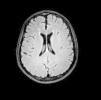

A 19-year-old male presented with asthenia, abdominal pain, vomiting, fever, jaundice, and rash. The patient quickly progressed to severe shock, purple lower limbs and toes necrosis. The diagnosis of Rickettsia spp (gene regions surveyed gltA (TaqMan) and internal control of the human RNAse P reaction) was made by PCR (polymerase chain reaction) of serum sample. Serial serology, with indirect immunofluorescence, also turned out positive with increasing IgG titers, initially <1/64 and then >1/256 two weeks later. The patient went on to present nystagmus and conjugate eye deviation. Magnetic resonance imaging (MRI) identified: multiple foci of marked hypointensity on susceptibility weighted imaging (SWI), evidenced in the corpus callosum, deep white matter, bilateral basal ganglia, thalamus and middle cerebellar peduncles, compatible with hemosiderin deposits, possibly petechial hemorrhages (Fig. 1). Foci of hyperintensity were observed on T2/FLAIR weighted images in the semiovale centrum, deep white matter and periventricular regions (Figs. 2 and 3). The patient was treated with chloramphenicol but progressed with extremity necrotic lesions, requiring bilateral transmetal amputation of toes and at the proximal phalanx of second, third, fourth, and fifth fingers of the right hand. He was discharged after 55 days of hospitalization for outpatient follow-up.

Dissemination to the central nervous system (CNS) occurs by hematogenous spread, with invasion of arterioles and capillaries, leading to inflammation and rupture of the blood–brain barrier. The possible findings on MRI include meningeal enhancement, varying degrees of swelling and periventricular and subcortical infarction, secondary to vasculitis, which tend to occur in a perivascular distribution, as observed in this case (which can mimic demyelinating disease).2,3 The CT scans of the head can be normal or show diffuse white matter changes, sulcal effacement and/or focal hypodensities consistent with infarctions.4 However, MRI is the exam that better characterizes CNS involvement in this entity, evidencing both multifocal hemorrhages and the foci of white matter changes due to vasculitis.